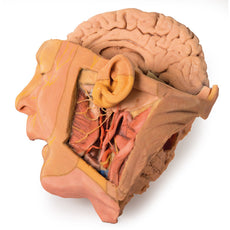

The face: On the right side of the head the parotid gland has been removed to reveal the facial nerve and all its branches (temporal, zygomatic, buccal, marginal mandibular and cervical) and demonstrate the spatial relations of structures embedded in the gland from superficial to deep (facial nerve, retromandibular vein, external carotid artery). In the surrounding region the temporalis, masseter and posterior belly of digastric are exposed, as are and the facial artery, transverse facial artery and superficial temporal artery. The facial vein and transverse facial vein are clearly visible uniting to form the common facial vein which is joined by the retromandibular vein to form the external jugular vein.

Viewed from the anterior aspect the face has been dissected to display some of the facial muscles around the mouth (buccinator [on the left], orbicularis oris and zygomaticus major). On the left side of the infratemporal fossa has been open to expose the medial and lateral pterygoids.

The lateral pterygoid is divided to show the mandibular division of the trigeminal nerve dividing into the lingual nerve and the inferior alveolar branch. Also on the left side the branches of the ophthalmic division of the trigeminal that supply the skin above the eyebrows and scalp (supraorbital [left only] and supratrochlear nerves [both sides]) are dissected. The submandibular gland is clearly visible below the mandible on both sides as are the facial arteries and veins as they course over the mandible.

The neck: The musculoskeletal portion of the neck have been removed to display the pharynx posteriorly, the larynx anteriorly, and the neurovascular bundles laterally. The suprahyoid and infrahyoid muscles can be seen on the neck, as well as the cricothyroid muscle.

When looking up the length of the trachea from below, the vocal folds are visible. The hypoglossal nerve can be seen winding around the lateral surface of the external carotid artery and the external branch of superior laryngeal nerve is seen descending in the neck. The internal jugular vein, the common carotid artery and its bifurcation into external and internal carotid arteries are clearly seen on both left and right. The vagus nerve in the carotid sheath is also visible. The ansa cervicalis is visible emerging below the digastric muscle and descending on the surface of the internal jugular vein. The internal branch of the superior laryngeal nerve can be seen below the superior thyroid artery on the left. The superior thyroid artery branching from the external carotid artery is seen descending in the anterior neck. The internal branch of the superior laryngeal artery is visible on the left piercing the thyrohyoid membrane above the inferior constrictor where this muscle is attached to the hyoid bone.

This 3D print specimen preserves a series of features of the head and visceral column of the neck:The face: On the right side of the head the parotid gland has been removed to reveal the facial nerve and all its branches (temporal, zygomatic, buccal, marginal mandibular and cervical) and demonstrate the spatial relations of structures embedded in the gland from superficial to deep (facial nerve, retromandibular vein, external carotid artery). In the surrounding region the temporalis, masseter and posterior belly of digastric are exposed, as are and the facial artery, transverse facial artery and superficial temporal artery. The facial vein and transverse facial vein are clearly visible uniting to form the common facial vein which is joined by the retromandibular vein to form the external jugular vein.

Viewed from the anterior aspect the face has been dissected to display some of the facial muscles around the mouth (buccinator [on the left], orbicularis oris and zygomaticus major). On the left side of the infratemporal fossa has been open to expose the medial and lateral pterygoids.

The lateral pterygoid is divided to show the mandibular division of the trigeminal nerve dividing into the lingual nerve and the inferior alveolar branch. Also on the left side the branches of the ophthalmic division of the trigeminal that supply the skin above the eyebrows and scalp (supraorbital [left only] and supratrochlear nerves [both sides]) are dissected. The submandibular gland is clearly visible below the mandible on both sides as are the facial arteries and veins as they course over the mandible.

The neck: The musculoskeletal portion of the neck have been removed to display the pharynx posteriorly, the larynx anteriorly, and the neurovascular bundles laterally. The suprahyoid and infrahyoid muscles can be seen on the neck, as well as the cricothyroid muscle.

When looking up the length of the trachea from below, the vocal folds are visible. The hypoglossal nerve can be seen winding around the lateral surface of the external carotid artery and the external branch of superior laryngeal nerve is seen descending in the neck. The internal jugular vein, the common carotid artery and its bifurcation into external and internal carotid arteries are clearly seen on both left and right. The vagus nerve in the carotid sheath is also visible. The ansa cervicalis is visible emerging below the digastric muscle and descending on the surface of the internal jugular vein. The internal branch of the superior laryngeal nerve can be seen below the superior thyroid artery on the left. The superior thyroid artery branching from the external carotid artery is seen descending in the anterior neck. The internal branch of the superior laryngeal artery is visible on the left piercing the thyrohyoid membrane above the inferior constrictor where this muscle is attached to the hyoid bone.